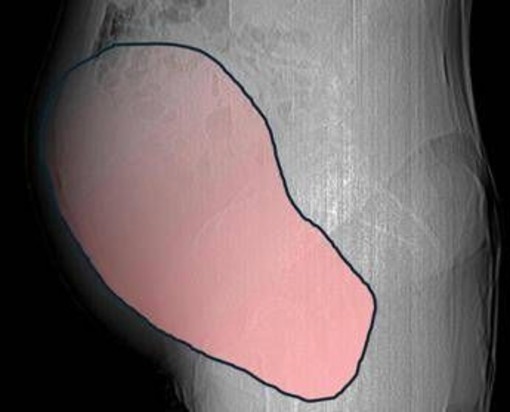

(Adnkronos) - Una donna di 69 anni ha scoperto di essere affetta da un tumore ovarico di dimensioni eccezionali, paragonabili a quelle di una gravidanza gemellare a termine, solo quando il suo organismo ha improvvisamente iniziato a cedere. Per mesi la gigantesca cisti ovarica, con un diametro di circa 28 centimetri, è rimasta nascosta, senza dare segnali evidenti. La paziente non si era accorta di nulla. L’allarme è scattato quando la massa, associata alla presenza di una seconda neoplasia intestinale, ha iniziato a comprimere il colon, provocando sintomi acuti ed improvvisi fino ad una grave difficoltà intestinale non più ignorabile. A riferire la storia è l'ospedale Sant'Anna di Torino.

Il caso risale a metà dicembre quando la donna arriva all’attenzione dei sanitari e a prendere in carico il caso è la Chirurgia Ginecologica Mininvasiva dell'ospedale Sant’Anna diretta dal dottor Paolo Petruzzelli. I tempi sono strettissimi, con le festività natalizie alle porte, ma la risposta è immediata: in pochi giorni si definisce l'inquadramento diagnostico, stadiazione e percorso terapeutico. Il 23 dicembre, a poche ore dalla vigilia di Natale, la paziente entra in sala operatoria. L’intervento dura circa sei ore. ''Durante l’intervento emerge tutta la gravità della situazione - spiegano dall'ospedale - La gigantesca neoplasia ovarica viene asportata: pesa circa 6 chilogrammi, con un volume paragonabile a quello di una gravidanza gemellare a termine. Ma non è l’unica minaccia. I sintomi più pericolosi sono legati alla sofferenza intestinale, che richiede un intervento immediato e coordinato di più specialisti''.